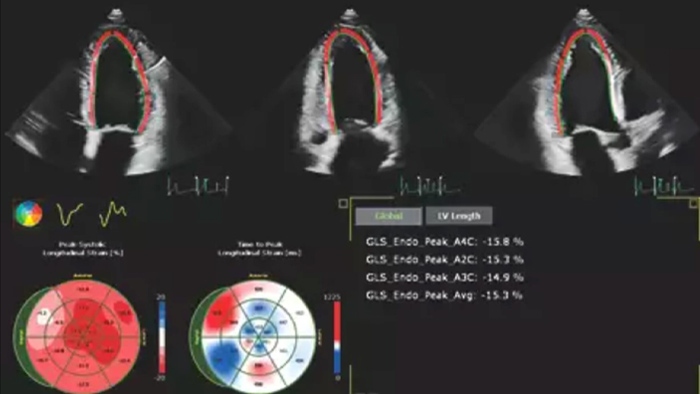

Fast and reproducible tools with integrated workflows

Robust and reproducible imaging tools are important to diagnose and monitor disease progression in heart failure. Current guidelines support the use of advanced echocardiography tools such as longitudinal strain and 3D assessment of LV and RV volumes and function.

Image showing results of automation for robust, proven reproducible cardiac quantification in both 2D and 3D

Automation for robust, proven reproducible cardiac quantification in both 2D and 3D.